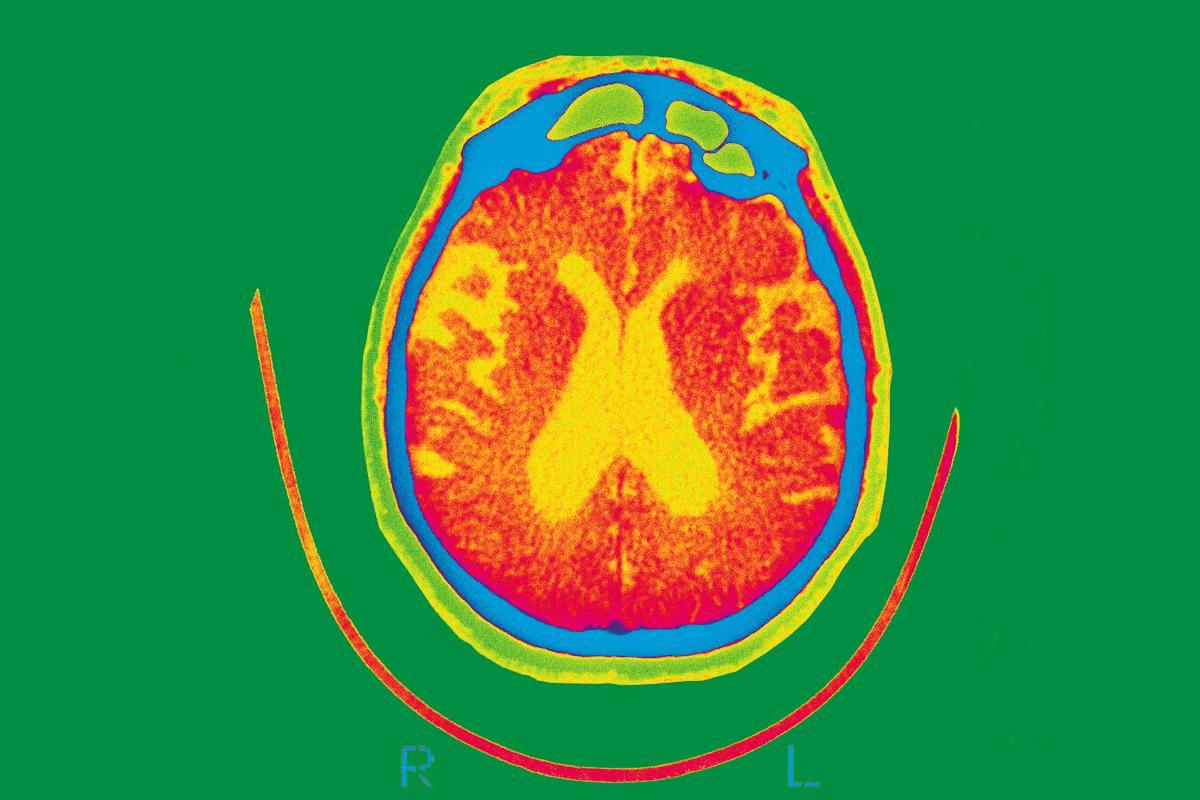

Brain Imaging in Alzheimer’s Diagnosis

Brain imaging is key in diagnosing Alzheimer’s disease. It gives us a look at how the brain works and its structure. We use different imaging methods to check for other conditions that might look like Alzheimer’s. This helps us make sure we have the right diagnosis.

Revealing Brain Structure Changes

MRI scans are very important in diagnosing Alzheimer’s. They show detailed images of the brain. MRI scans can spot changes like hippocampal atrophy, which is a sign of Alzheimer’s.

They can also find other problems like tumors or strokes. These can also affect how well we think.

Diagnostic Role of CT Scans

CT scans are used at the start to check for Alzheimer’s. They are good at finding big problems like bleeding or strokes. These can cause thinking problems.

Even though CT scans aren’t as good as MRI for Alzheimer’s signs, they are easy to get. They can give us quick, important information.

Advanced Functional Imaging Techniques

Advanced functional imaging techniques give us more information. They show how the brain works and how it uses energy. PET scans can spot amyloid and tau, which are signs of Alzheimer’s.

Functional MRI (fMRI) looks at how brain activity changes. This helps us understand how Alzheimer’s affects the brain.

By using all these imaging methods together, we can get a better understanding of Alzheimer’s. This helps us find the right treatment and care for each person.